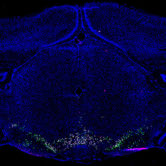

Researchers at the University of Alabama at Birmingham have mapped 16 groups of cells that play a key role in how dopamine and other neurotransmitters travel through the brain. By identifying the cell groups in the brain's ventral tegmental area, UAB researchers laid the building blocks for future research on how the groups interact and connect to the rest of the brain in people with addiction, attention-deficit/hyperactivity disorder and other neurological conditions.